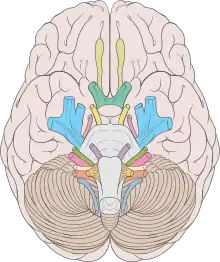

| Cranial nerves | |

Cranial nerve disease is an impaired functioning of one of the twelve cranial nerves. Although it could theoretically be considered a mononeuropathy, it is not considered as such under MeSH.

It is possible for a disorder of more than one cranial nerve to occur at the same time, if a trauma occurs at a location where many cranial nerves run together, such as the jugular fossa. A brainstem lesion could also cause impaired functioning of multiple cranial nerves, but this condition would likely also be accompanied by distal motor impairment.